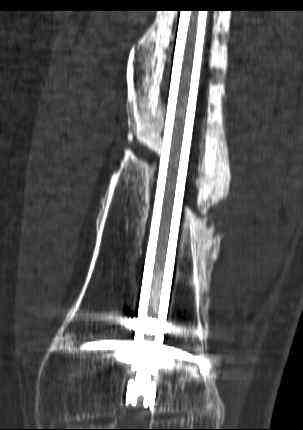

feb 07: retrograde nail + bone graft + BMP

may 07: dynamisation nail

sept 07: locking screw removal (max. dynamisation reached)

nov 07: persistant non-union distal femur; other fractures healed uneventfully.

All with gradual/partial weightbearing etc. Currently 50-100% weight bearing, no pain.

Soft tissues are intact. No smoking or diabetes.CRP <2

What would you do?